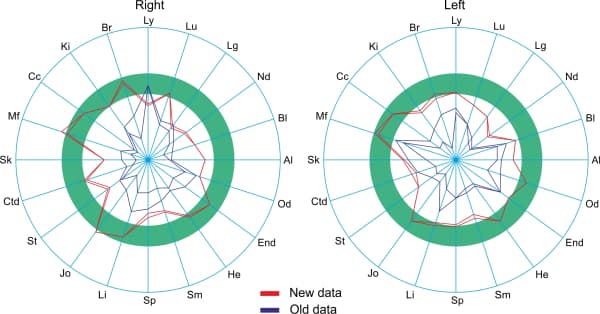

As Figure 2 illustrates, the activity of the majority of the organs and systems falls in the normal range before the mobile phone conversation.

Figure 3 shows a dramatic reduction in the activity of body systems such as the immune, endocrine, circulatory, and gastrointestinal systems, as a result of a 3-minute mobile phone conversation.

Figure 4 illustrates changes in the activity of organs and body systems after a three-minute phone conversation using the same mobile phone, but protected with an Aires Shield electromagnetic anomaly neutralizer. Not only are the measures restored, the are improved when compared to the baseline measurements.

Figure 5 illustrates the changes in the electric potential of the circulatory systems control points when under the influence of electromagnetic radiation from a mobile phone (second column in the diagram) in comparison with the baseline radiation (first column) and radiation with the Aires Shield (third column).

Note not only the sharp reduction in the electric potential of the circulatory system under the influence of electromagnetic radiation from the mobile phone to the level of developing progressive dystrophic changes in the system, but the obvious effect of the drop in electric potential (indicated in red), which indicates pronounced astenization and a distruption of neuroendocrinal regulation and vegetative balance.

The Aires Shield electromagnetic anomaly neutralizer both fully restores the electric potential and eliminates the progress of astenization, saving resources for the body.

The behavior of the total deviation from the electric potential norm clearly illustrates the affect of a mobile phone’s electromagnetic radiation and the Aires Shield electromagnetic anomaly neutralizer on the activity of organs and body systems. The value is 0 at the norm.

Figure 6 presents the total deviation from the electric potential norm at various stages of the experiment.

It can be seen that a three-minute mobile phone conversation reduces the activity of organs and tissues in basically healthy people by an average of 30%, which coincides with data from the WHO. People with more pronounced electric potential deviations (up to 40% from the norm), the negative affect of the mobile phone’s electromagnetic radiation is more apparent and reaches 50%, but the Aires Shield electromagnetic anomaly neutralizer not only protects the body from the affects of the man-made radiation, it also promotes restoration of the disrupted activity.

The Aires Shield stabilizes this restorative effect for several hours.